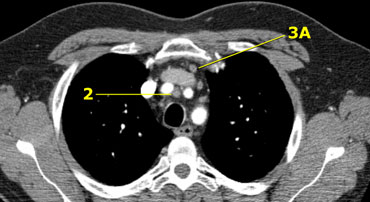

On the left a station 2 node in front of the trachea, i.e. a 2R-node.

There is also a small prevascular node, i.e. a station 3A node.

3. Prevascular and Prevertabral nodes

Station 3 nodes are not adjacent to the trachea like station 2 nodes.

They are either:

3A anterior to the vessels or

3B behind the esophagus, which lies prevertebrally.

Station 3 nodes are not accessible with mediastinoscopy.

3P nodes can be accessible with endoscopic ultrasound (EUS).

On the left a 3A node in the prevascular space.

Notice also lower paratracheal nodes on the right, i.e. 4R nodes.